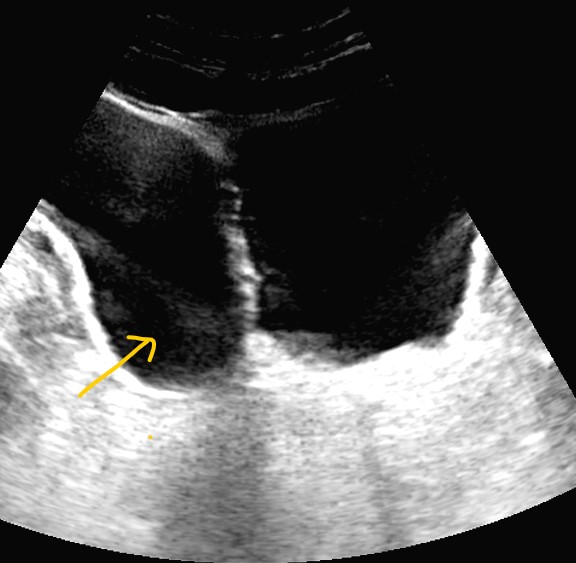

Riñones de tamaño y morfología normales. No observamos litiasis ni dilatación de la vía urinaria. A nivel de la vejiga presenta un tabique con comunicación a una gran cavidad en la pared lateral derecha que da la impresión de que existen dos vejigas urinarias. No hay lesiones parietales. Próstata 32 cc. Volumen premiccional de la cavidad mayor 350 cc y posmiccional 210 cc.

Vejiga urinaria con presencia de jets ureterales, de paredes lisas con un gran divertículo en la pared lateral derecha de 543 cc premiccional que vacía a la mitad en posmiccional 310cc (57%).Volumen vesical premiccional 620cc y posmiccional 179 cc (28%).